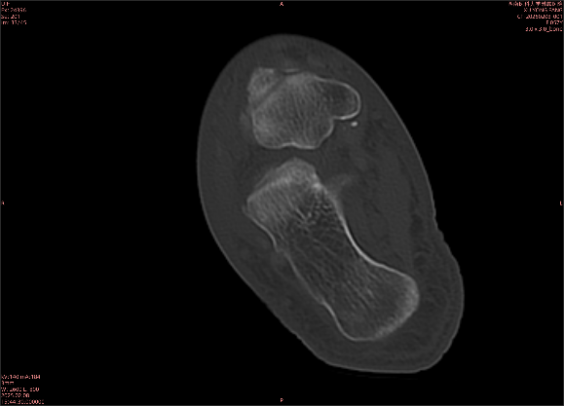

舉例圖像

圖1

圖2

專業(yè)解釋看不懂沒關(guān)系,大家看圖1和圖2就可以了,這是同一個(gè)患者跟骨的磁共振和CT圖像,圖1的紅色箭頭指示的黑線就是磁共振圖像顯示的骨折線,一目了然。而對(duì)比圖2的CT圖像上并未顯示異常。